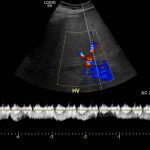

- Heterogeneous hypoechoic lesion in the periphery of the right hepatic lobe measuring up to 5.5 cm without internal vascularity

- Abscesses should not have internal vascularity (but remember that necrotic neoplasms may not have internal vascularity either)